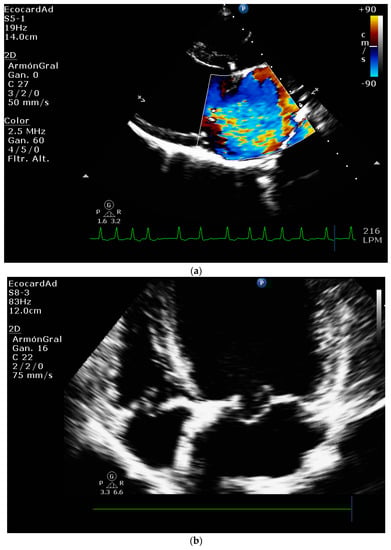

4.8.1. Evaluation of the Regurgitant Area

4.8.2. Presence of Vena Contracta